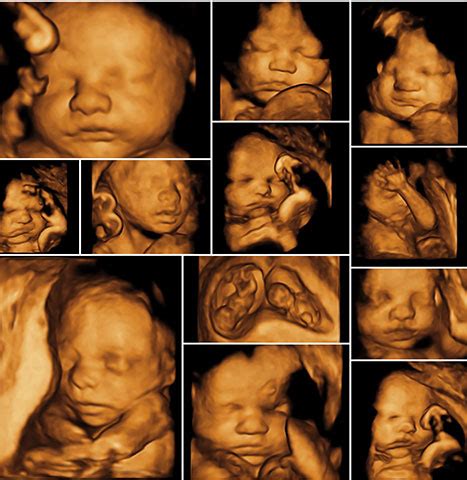

Je tiež dôležité rozlišovať medzi klasickým morfologickým ultrazvukom a 3D/4D ultrazvukom. Morfologický ultrazvuk je primárne diagnostické vyšetrenie zamerané na detekciu vrodených chýb, zatiaľ čo 3D/4D ultrazvuk poskytuje obraz dieťaťa v reálnom čase a často sa vykonáva skôr pre estetické alebo emocionálne dôvody. Niektoré ženy uvádzajú, že morfologický ultrazvuk nie je 3D, a že sa jedná o dve samostatné vyšetrenia.